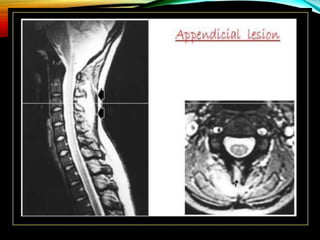

4.APPENDICIAL

• Isolated infection involving

pedicles , laminae (neural

arch), transverse processes, &

spinous process.

• Uncommon lesion (< 5%).

• In conjunction with the

typical paradiscal variant

in 30%.

• Rarely present as synovitis of

facet joints.

4. APPENDICIAL LESIONS :